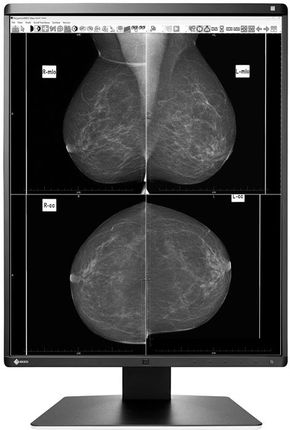

21,3″ (54,1 cm) | 2048 x 2560 (4:5) | IPS GX560 MammoDuo wyświetla szczegółowe obrazy mammograficzne oraz obrazy drobnych struktur w wysokiej rozdzielczości. Dwa ekrany w rozdzielczości po 5 megapikselli i wysoki poziom luminancji zapewniają doskonałą reprodukcję obrazu. Jasność i kontrast monitora GX560 MammoDuo umożliwiają wyświetlanie głębokich czerni i krzywej luminancji zgodnej ze standardem DICOM. Dzięki dwóm ekranom w rozdzielczości 5 MP, zamocowanym na specjalnej podwójnej stopce, model MammoDuo doskonale nadaje się do wyświetlania obrazów z mammografii i tomosyntezy.

21,3″ (54,1 cm) | 2048 x 2560 (4:5) | IPS GX560 MammoDuo wyświetla szczegółowe obrazy mammograficzne oraz obrazy drobnych struktur w wysokiej rozdzielczości. Dwa ekrany w rozdzielczości po 5 megapikselli i wysoki poziom luminancji zapewniają doskonałą reprodukcję obrazu. Jasność i kontrast monitora GX560 MammoDuo umożliwiają wyświetlanie głębokich czerni i krzywej luminancji zgodnej ze standardem DICOM. Dzięki dwóm ekranom w rozdzielczości 5 MP, zamocowanym na specjalnej podwójnej stopce, model MammoDuo doskonale nadaje się do wyświetlania obrazów z mammografii i tomosyntezy.

Doskonałe odwzorowanie detaliDzięki rozdzielczości dwa razy po 5 MP, współczynnikowi kontrastu 1700:1 i stabilnej jasności na poziomie do 2500 cd/m2 monitor zapewnia doskonałą jakość obrazu. Różnice między najdrobniejszymi detalami widoczne są niezależnie od kąta patrzenia. To przydatne zwłaszcza w sytuacji, gdy ekran ogląda kilka osób jednocześnie.

Stanowisko dwuekranowe bez rozpraszających ramekGX560 ma ramkę o szerokości zaledwie 7,5 mm – najcieńszą spośród wszystkich 5-megapikselowych monitorów dostępnych na rynku. Dzięki niej całkowita odległość między dwoma ekranami wynosi tylko 15 mm. Na dodatek ramka znajduje się jedynie 2,5 mm powyżej ekranu, co pozwala uzyskać niemal idealnie płaską powierzchnię w konfiguracji dwumonitorowej.

Doskonałe odwzorowanie detaliDzięki rozdzielczości dwa razy po 5 MP, współczynnikowi kontrastu 1700:1 i stabilnej jasności na poziomie do 2500 cd/m2 monitor zapewnia doskonałą jakość obrazu. Różnice między najdrobniejszymi detalami widoczne są niezależnie od kąta patrzenia. To przydatne zwłaszcza w sytuacji, gdy ekran ogląda kilka osób jednocześnie.

Stanowisko dwuekranowe bez rozpraszających ramekGX560 ma ramkę o szerokości zaledwie 7,5 mm – najcieńszą spośród wszystkich 5-megapikselowych monitorów dostępnych na rynku. Dzięki niej całkowita odległość między dwoma ekranami wynosi tylko 15 mm. Na dodatek ramka znajduje się jedynie 2,5 mm powyżej ekranu, co pozwala uzyskać niemal idealnie płaską powierzchnię w konfiguracji dwumonitorowej.